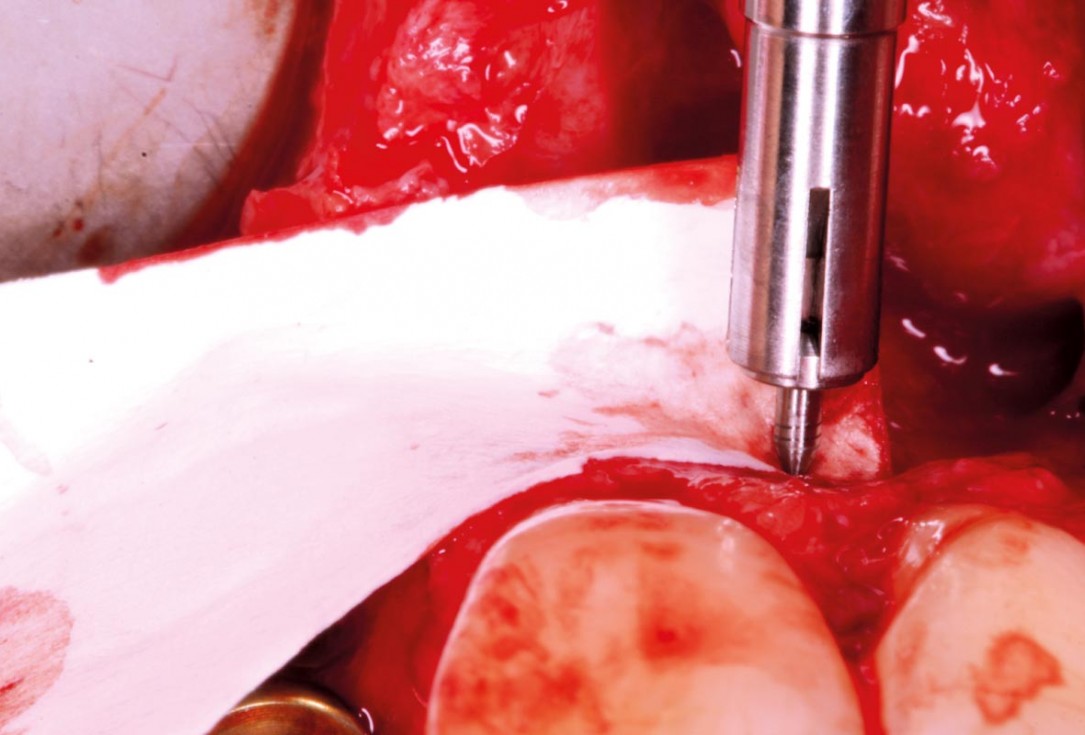

02/20 - Guided bone regeneration after implant placement using Jason® membrane with good pin stabilisation.Delayed implant placement with GBR and soft tissue augmentation at the aesthetic area - 2 years follow up – Dr. H. Maghaireh & Dr. V. Ivancheva

03/20 - Exposed implant threads covered with a thin layer of autogenous bone chips harvested during implant bed preparation.Delayed implant placement with GBR and soft tissue augmentation at the aesthetic area - 2 years follow up – Dr. H. Maghaireh & Dr. V. Ivancheva